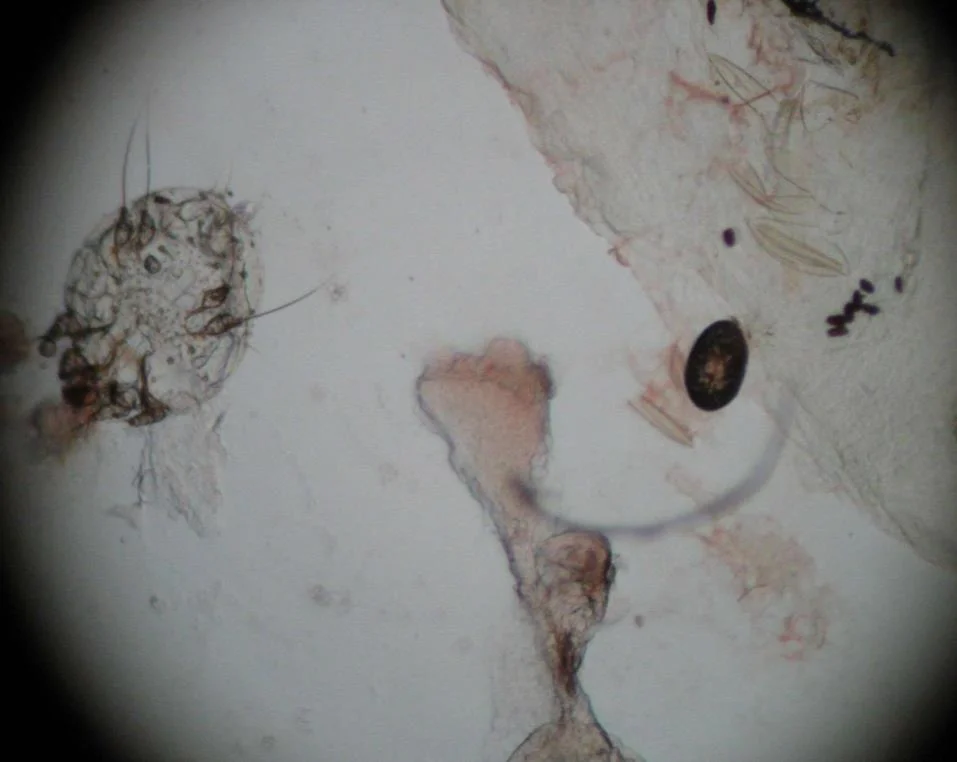

What investigation is done to confirm the diagnosis? / What in-office procedure would best help to confirm the diagnosis of scabies?

- Skin scraping (mineral oil preparation) + microscopic examination.

What will you see?

- Mites, eggs, and scybala (feces).